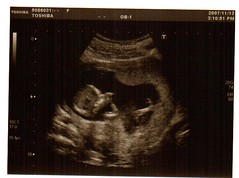

一個禮拜前,老婆跟我到產科去做懷孕12~14周的唐氏兒篩檢,包括超音波測量胎兒的後頸透明帶厚度和抽血檢查。那天,還是我看健診的時段,祈禱當天來看報告的病人不多,可以趕上老婆照超音波的時間,老天爺還真給面子,病人來得都很密集,而且小寶貝一開始也不肯好好躺著,所以老婆只能先散步,等到小寶貝翻身後,躺出適合照超音波,可以測量頸後透明帶的姿勢。

老婆剛躺到超音波檢查台沒多久,我剛好也趕到檢查室,馬上看到小寶貝在老婆的子宮裡調皮翻滾的樣子,雖然我們希望可以找到最佳的姿勢,以得到後頸透明帶最正確的厚度,不過也是託小寶貝調皮的福,讓老婆跟我看了許多小寶貝的畫面。雖然只有12~13周的年紀,不過小寶貝想要伸展身手的活力,倒是很強,有時向左滾,有時又向右轉,還可以看到他(她)伸懶腰的樣子,實在很可愛呢~~如果從側面看小寶貝,已經可以看到顯而易見的鼻骨、上頷骨,當然還有那棵一分鐘會跳動一百多下的小心臟,而那噗通噗通的心跳,大概是世界上最具生命力和最美麗,和最有希望的聲音了。

仔細看超音波下的小寶貝,很難想像老婆的肚子裡,正孕育一個新的生命,不知道現在小寶貝可不可以聽到外界的聲音,我想我們要照老婆跟我之前的計畫,好好讓小寶貝聽音樂,避免到時後跟爸爸一樣五音不全,沒有一個音抓的準。所以呢….希望小寶貝配著我們的精選音樂,可以在媽媽的子宮裡愉快的配合節拍,翻滾吧!小寶貝